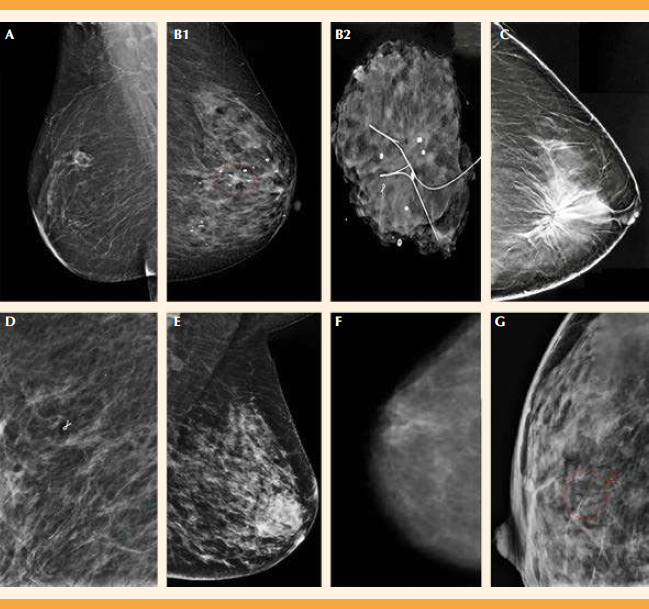

Su incidencia constituye entre el 3 y el 17% de las cirugías de las lesiones benignas de mama, lesiones sintomáticas o detectadas mediante programas de tamizaje; sin embargo, su incidencia real podría estar infraestimada porque no todas las imágenes radiológicas cumplen con criterios sospechosos de malignidad (Figura 1) y, por ende, no se confirman histológicamente.14,15

A1) carcinoma lobulillar in situ: Se considera una lesión que pasa inadvertida, no hay un patrón imagenológico específico, pero las microcalcificaciones son el hallazgo más frecuente, suelen estar agrupadas, puntiformes y de alta densidad. B1) carcinoma ductal in situ: Se pueden apreciar microcalcificaciones dispersas, lo cual es lo más común. Pueden ser pleomórficas y lineales finas ramificadas. B2) carcinoma ductal in situ: Biopsia escisional, con previo marcaje. Se observan microcalcificaciones que hacen sospechar de malignidad. C) Cicatriz radial: La lesión clásica suele mostrar un área de distorsión de la arquitectura con centro radiolúcido, espículas delgadas y “estrella negra” en la mastografía. D) Hiperplasia ductal atípica: Los hallazgos más característicos son las microcalcificaciones, que suelen ser pleomórficas finas y también lineales finas o ramificadas. Suele coexistir con adenosis esclerosante. Menos del 50% forman espacios necróticos. E) Adenosis esclerosante: No existe un patrón mastográfico característico. Las anormalidades más comunes son microcalcificaciones, nódulos, asimetría focal y distorsión de la arquitectura. F) Papiloma intraductal: Se observan calcificaciones puntiformes y brillantes dispersas. Realmente, los hallazgos son inespecíficos, el hallazgo más frecuente son los nódulos únicos o múltiples. G) Lesiónmucocele-like: las lesiones que hacen sospechar de malignidad o que sugieren un estudio más a fondo son las que muestran microcalcificaciones pleomórficas, masas redondas, ovaladas o irregulares, márgenes indistintos, espiculados, microlobulados, oscurecidos o alta densidad mamaria.

Figura 1 Patrón mastográfico de las lesiones premalignas de mama.